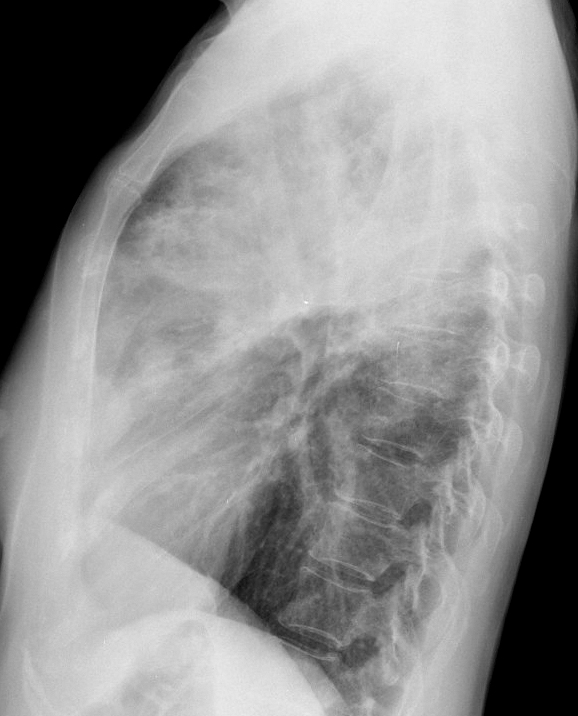

Gallery Pneumonia Case 13 RUL pneum Lat

Case 13 RUL pneum Lat